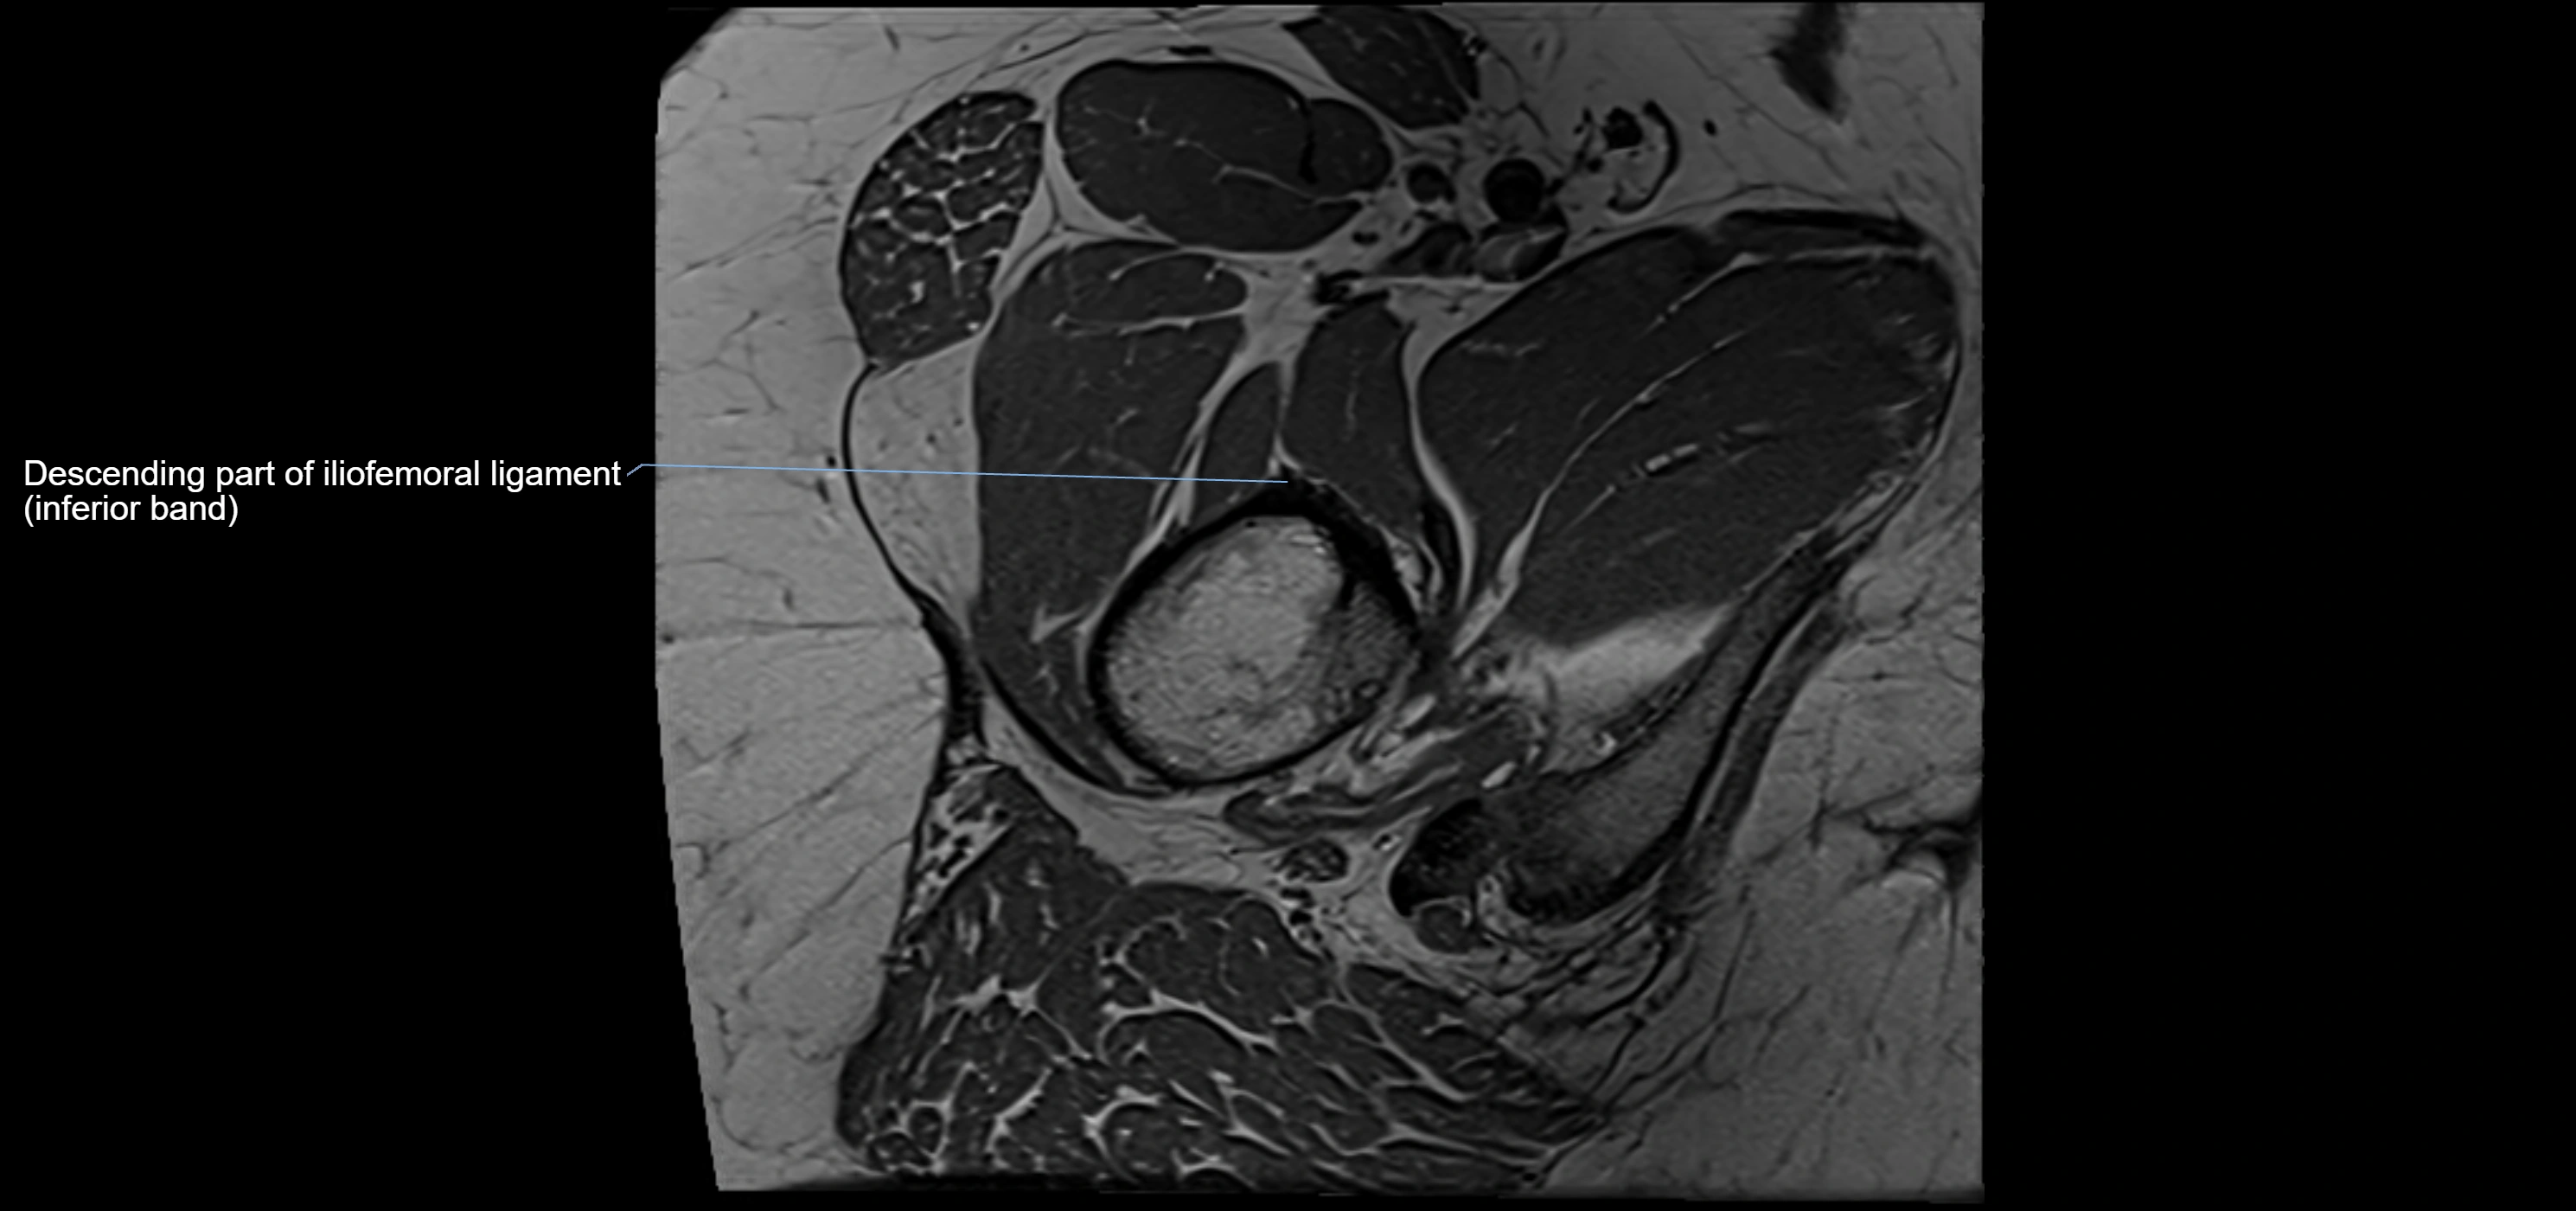

MRI image

image